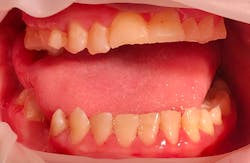

Katie presented with multiple areas of dental decay, heavy plaque buildup, and light to moderate supragingival calculus with little subgingival calculus. There are signs of bruxism with wear and small fractures on her teeth (figures 1 and 2). Katie has a large tongue that often covers her teeth while her mouth is open (figure 3). She has an anterior and posterior crossbite (figure 4) and a retained primary tooth. Katie was cooperative for radiographs, which were taken while working with her verbally and using positive wording and demonstrations. Extra time was taken to allow her to process what was being described and to abate her fears.